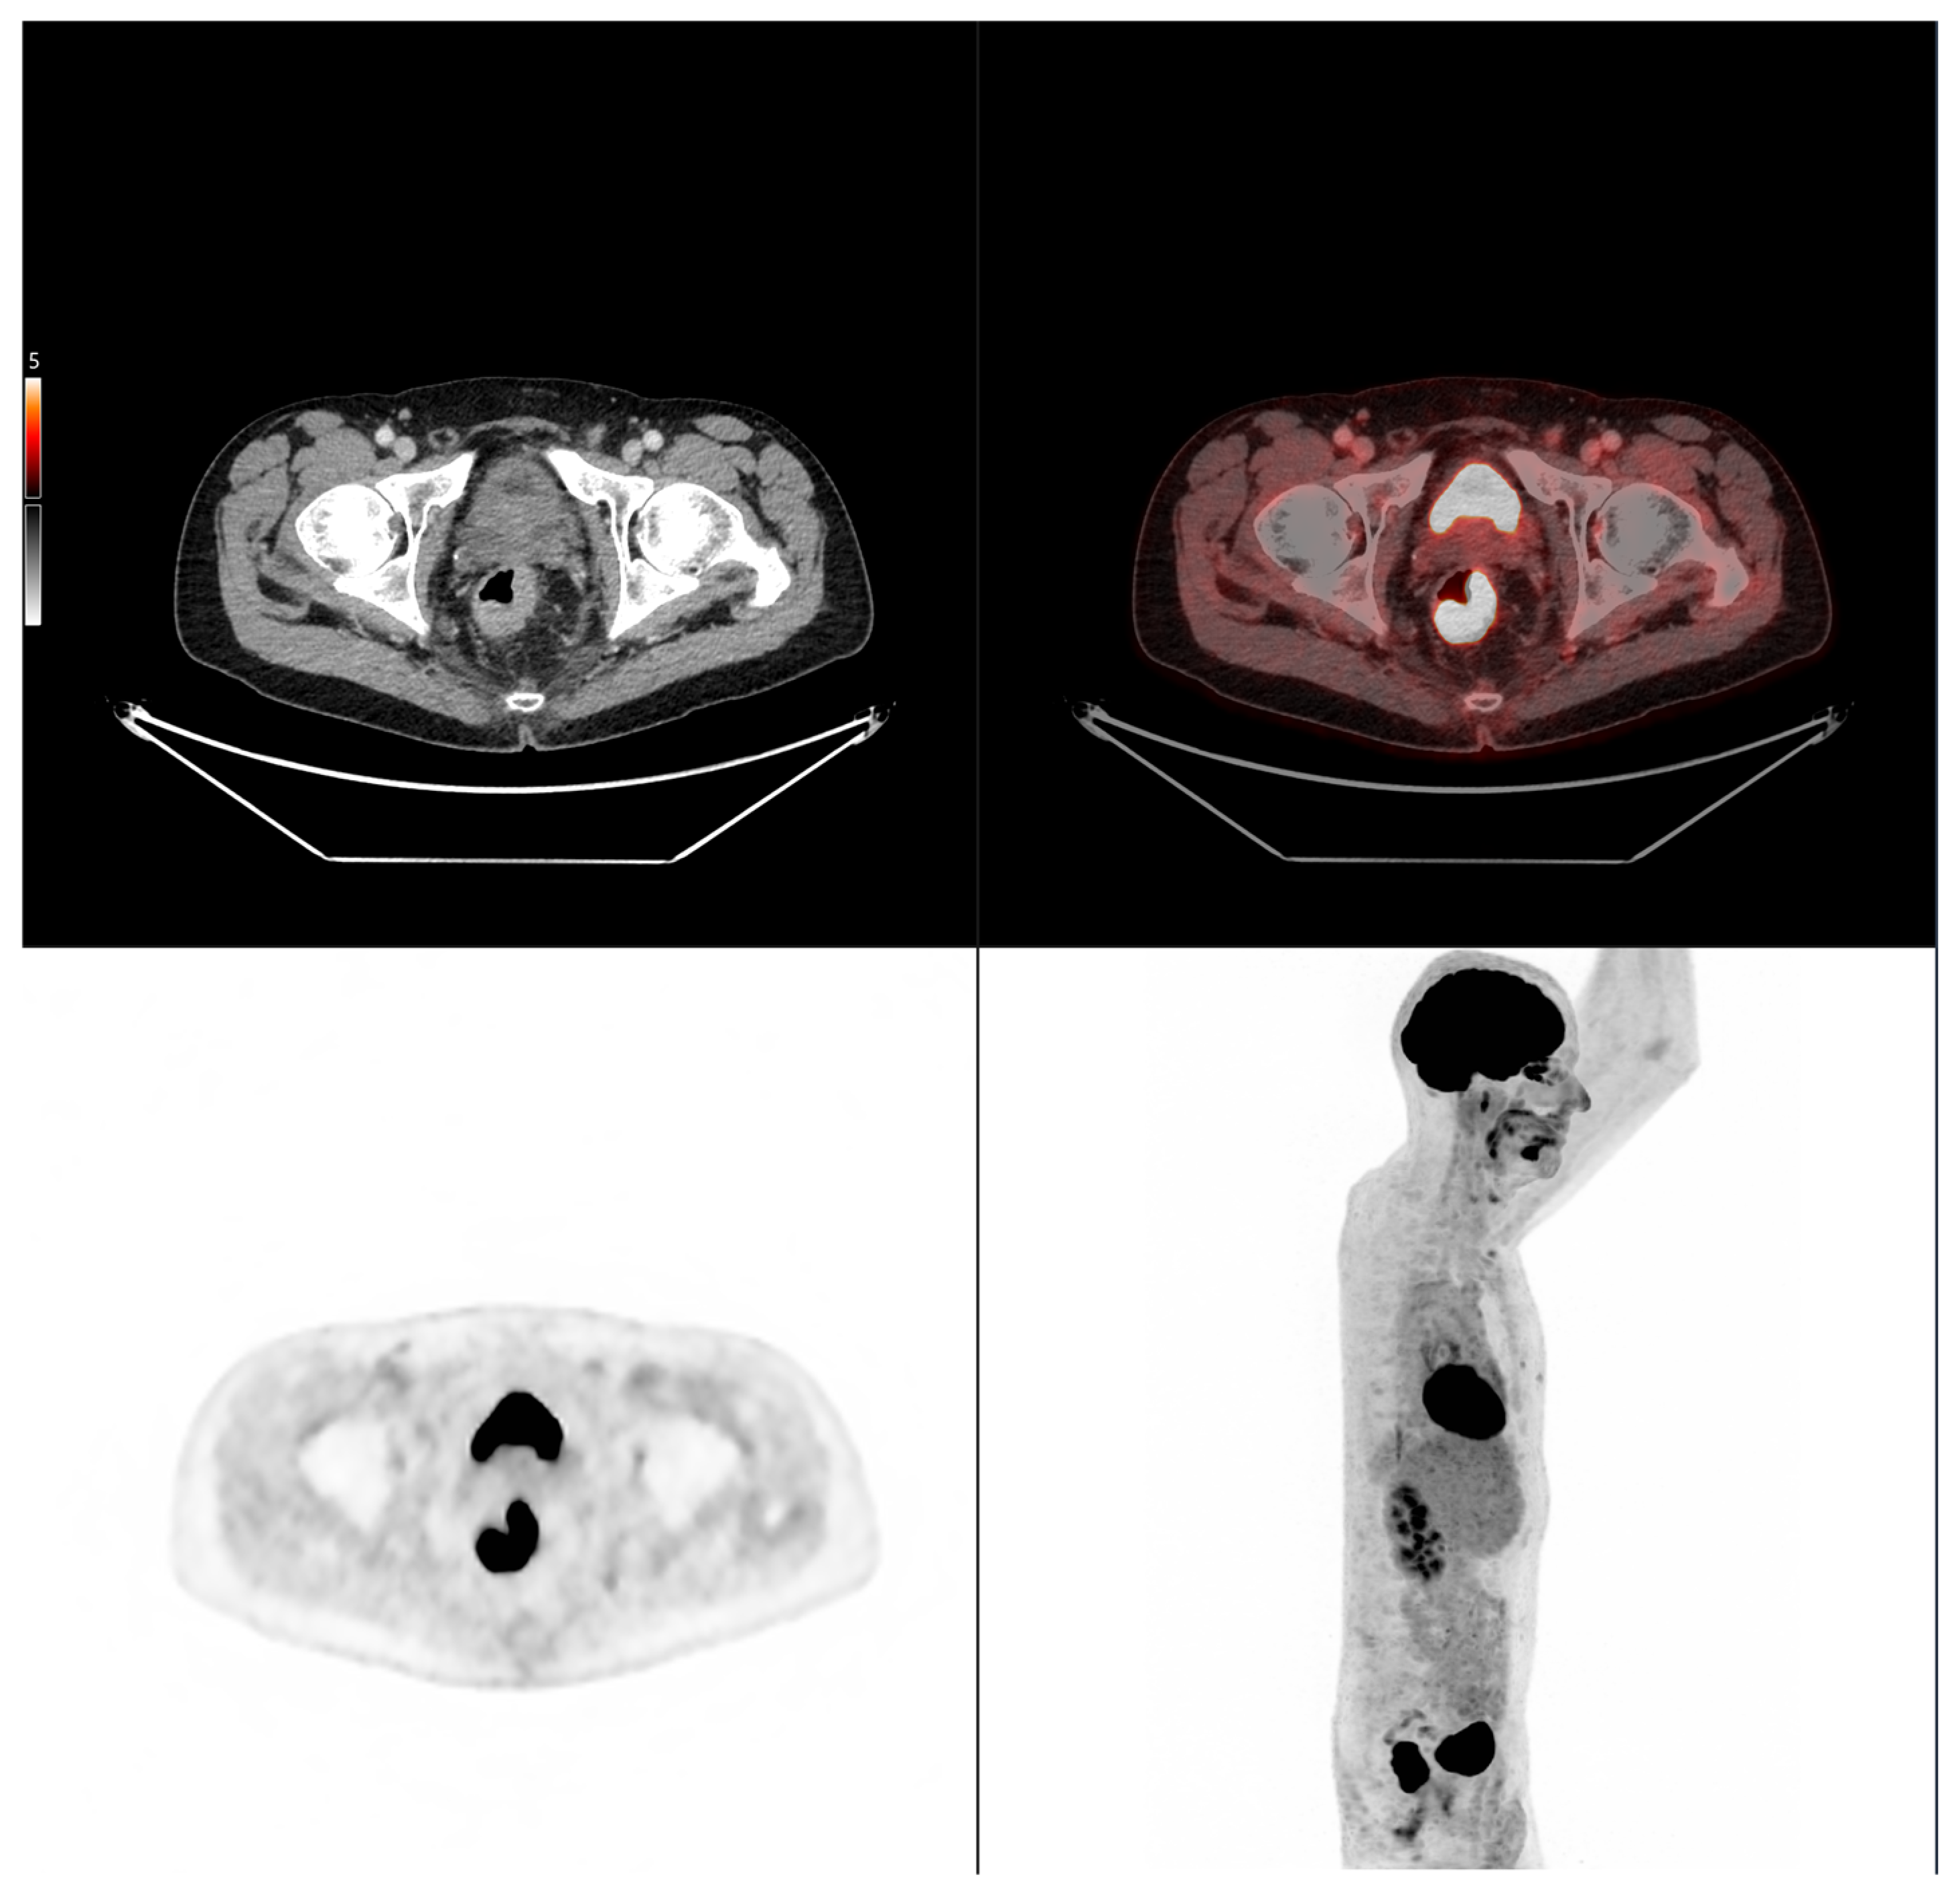

Case 2: A 69-year-old patient with stage IIA rectal cancer, presenting with a semi-circumferential primary tumor with craniocaudal extension and MTV both below the predictive cut-offs (5.1 cm vs. 6.2 cm; MTV 10.1 vs. 35.49 for OS and 32.08 for PFS). Baseline FDG PET/CT (top row) revealed intense hypermetabolism (SUVmax 38.8). Interim FDG PET/CT (bottom row) showed a good partial metabolic response, and the patient experienced sustained clinical benefit with no progression in the long term (OS = PFS = 29 months).

Figure 7. Representative example of manual delineation of a primary rectal tumor on baseline FDG PET/CT showing manual delineation of the metabolically active tumor volume (first row) on the PET image with corresponding fused PET/CT image and CT image with iodinated contrast medium (second row). Morphological features, including tumor shape (circular or semi-circular), cranio-caudal extension (in cm), and overall tumor volume (in cm3), were assessed on the CT image (often with contrast medium) coregistered with the PET images. Tumor shape was determined on the axial plane, cranio-caudal extension on the sagittal plane, and tumor volume after careful delineation on all planes. Iodinated contrast medium was administrated in 70% of cases after exclusion of contraindications. Metabolic parameters, including SUVmax, SUVmean, MTV and TLG, were systematically extracted from the segmented tumor (yellow in this figure). SUVmax (M in this figure) and TLG were automatically displayed. SUVmean could be obtained by simply replacing SUVmax with SUVmean in the parameter selection. MTV was automatically calculated from TLG and SUVmean values displayed on the workstation. The highlighted region in yellow represents the 3D contour of the primary tumor, excluding physiological uptake and non-tumor regions.